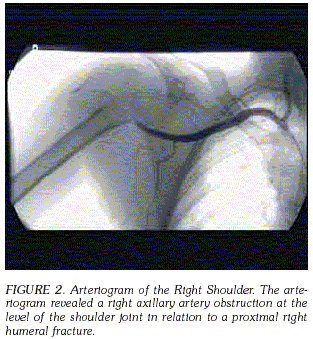

AXILLARY ARTERY INJURY SECONDARY TO HUMERAL NECK FRACTURE. CASE REPORT LESIÓN DE LA ARTERIA AXILAR SECUNDARIA A FRACTURA DEL CUELLO DEL HÚMERO. REPORTE DE CASO OSCAR JAVIER MANRIQUE M.Da*, RUBÉN PERALTA Ph.D.b Y MARGARITA APONTE M.D.c a Department of Surgery, Massachusetts General Hospital, Harvard Medical School, Boston, MA. * Correspondencia: omanrique@partners.org. Dirección postal: 31 Grove St. Unit B1; Boston, Massachusetts 02114, USA Phone: 617 459 8095. Abstract Fractures of the proximal humerus account over 75% of all humeral fractures in patients older than the age of 40 [1]. After the age of 50, women have a much higher incidence of these fractures than men, due to a higher incidence of osteoporosis. If the patient is less than 50 years old, high-energy trauma is the most common etiology. However, if the patient is over the age of 50, low energy mechanisms are more common [1]. Although axillary artery injury occurs frequently with dislocations of the shoulder and fractures of the clavicle, such injury is not commonly associated with fractures of the proximal humerus [2-5]. We present a patient with an axillary artery injury associated with a comminuted fracture of the proximal humerus. Key words: axillary artery, shoulder fractures. Las fracturas de húmero proximal corresponden al 75% de las fracturas en pacientes mayores de 40 años. Después de los 50 años y por su alta incidencia de osteoporosis, las mujeres tienen una mayor frecuencia de fracturas que los hombres. Y aunque en pacientes menores de 50 años el trauma de alto impacto es la causa principal de fractura, en pacientes que sobrepasan esa edad los mecanismos de bajo impacto son la causa más común. Las lesiones de la arteria axilar ocurren frecuentemente con dislocaciones de hombro y con fracturas de clavícula, no asociándose usualmente a fracturas del humero proximal. Presentamos el caso de una paciente con lesión de la arteria axilar asociada a una fractura conminuta de humero proximal. Usualmente el diagnóstico se sospecha por el cuadro clínico, teniendo en cuenta que durante el examen físico inicial, la circulación colateral del hombro puede demostrar pulsos normales, a pesar de que haya una lesión en la arteria axilar. Para tratar este tipo de lesiones el diagnóstico temprano es un elemento clave y para disminuir complicaciones futuras la circulación se debe restablecer en las primeras seis a ocho horas. De ahí la importancia de mantener un alto índice de sospecha cuando existen fracturas cercanas a grandes vasos y dada la anatomía vascular alrededor de la región proximal del humero, se debe descartar una lesión de la arteria axilar. Palabras clave: arteria axilar, fracturas proximales de húmero. Case Report A 69 year old female, fell at home from standing height, injuring her right shoulder. At the time of her fall, she described loss of sensation and motor function of her right hand. She initially presented to an outside hospital, and was then transferred to our institution for management of a right proximal humerus fracture-dislocation. It was noted by emergency medial personel during her transport that her right brachial and radial pulses were initially weak and subsequently became absent. Upon arrival at our institution, the right upper extremity had a palpable deformity and ecchymosis was present over the anterior aspect of her shoulder. The patient was unable to move her right hand fingers. She had decreased sensation in the median ulnar and radial nerve distribution. No brachial, ulnar or radial pulses were palpable or sensed by Doppler. Radiographic examination of her right shoulder revealed a comminuted fracture of the right proximal humerus (Figure 1). An angiogram was performed, showing occlusion of the right axillary artery at the level of the fracture, with reconstitution of the proximal brachial artery at the junction of the proximal/mid humeral diaphysis. No ulnar or radial arteries were visualized in the distal forearm (Figure 2). The patient was then taken to the operating room emergently.

There are several mechanisms by which the axillary artery can be injured in association with this type of fracture, and the regional anatomy that may predispose the artery to injury merits discussion. In the setting of a displaced fracture of the humeral surgical neck, the pull of the pectoralis major typically translates the diaphyseal component medially. The surgical neck of the humerus marks the level at which the anterior and posterior humeral circumflex vessels branch off of the axillary artery, passing anterior and posterior to the humeral diaphysis respectively, effectively tethering the artery to the humerus at this point. Additionally, if the humeral head dislocates as a result of the injury, it most commonly does so in an anterior, inferior direction, crowding the axilla and compressing the latter's neurovascular structures. Aside from laceration of the artery by bony fragments, there may be overstretching of the artery, which can lead to rupture, especially in an atheromatous artery [6,7]. Another important mechanism associated with fractures is intimal disruption and thrombosis [8]. With this mechanism of injury, the artery is stretched across the bony fragment and the adventitia remains intact while the fragile intima tears, leading to thrombosis. A patient with such an injury most commonly presents with an absent or diminished radial or brachial pulse[3]. Early recognition of these clinical signs is essential to avoid irreversible ischemic damage. Prompt arteriography is mandatory characterize fully any suspected arterial injury. Preoperative angiography is not only important to make accurate localization of the injury but can also provide important information regarding collateral flow. Nevertheless, certain emergent cases may necessitate intervention without the benefit of preoperative mapping.